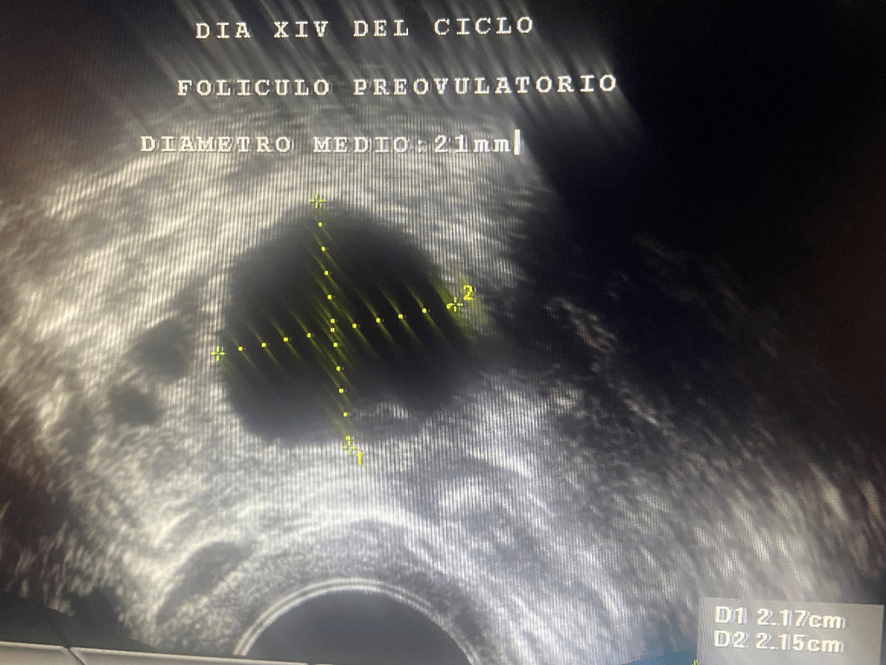

Además de estrógenos, este cuerpo lúteo empieza a segregar una hormona llamada Progesterona; la cual, es la causante de que el endometrio- que antes de la ovulación era proliferativo y con sus tres capas bien definidas- se transforme en un endometrio grueso, espeso e irregular. Se le conoce como “endometrio secretor”.

La producción de estrógenos y sobre todo de Progesterona, por parte del cuerpo lúteo, permanece durante unos 14 días, al cabo de los cuales, si no ha habido embarazo, bajan bruscamente los niveles de estas hormonas y aparece la menstruación. Se desprende y expulsa el endometrio. Empieza así un nuevo ciclo menstrual.

Sumando los 14 días que suele durar la fase folicular o proliferativa a los otros 14 que dura la fase lútea, luteínica o secretora, nos dan los 28 días que suele durar el ciclo menstrual.